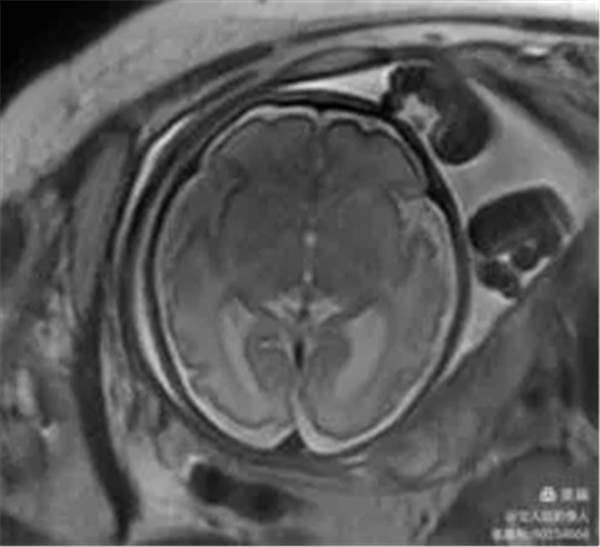

2、胎儿颅脑磁共振成像

病例12:评估胎儿颅脑发育情况。

图8,轴位T2WI-显示颅脑